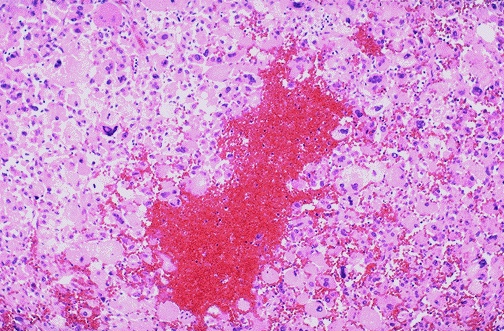

Image 7.5

At medium power, focal hemorrhage is present within this neoplasm.